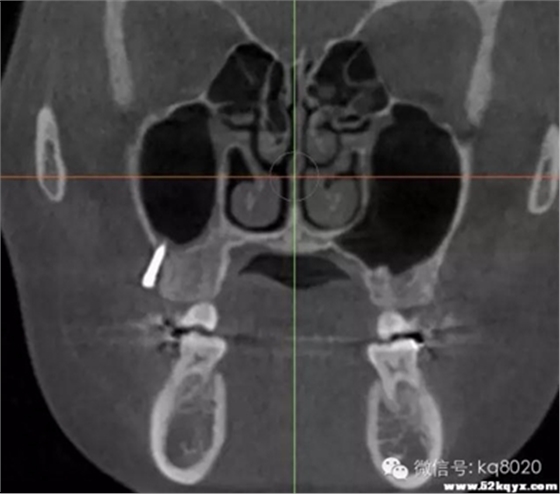

危險(xiǎn)因素:腭大動(dòng)靜脈及神經(jīng)出腭大孔后在距齦緣5-15mm距離向前直至切牙孔,植入部位不應(yīng)超過第二磨牙的遠(yuǎn)中,

以免傷及腭大孔;患者張口有限,會(huì)行成植入角度,容易觸碰牙根

植入位置和角度:牙根之間,冠狀面斜向下,避免過于水平未鉆入牙槽間隔,距離齦緣5mm處,

支抗釘與牙根成60°-70°角

大小:宜選用8×1.4mm支抗釘,并用彎機(jī)頭植入工具,以免支抗釘觸碰牙根

腭中縫兩側(cè)

危險(xiǎn)因素:腭中縫植入易穿破鼻竇;腭中縫尚未完全融合者,請離開中線5mm以上

植入位置和角度:垂直于骨面

大?。阂诉x用8×1.4mm支抗釘,并用彎機(jī)頭植入工具,方便垂直骨面進(jìn)入